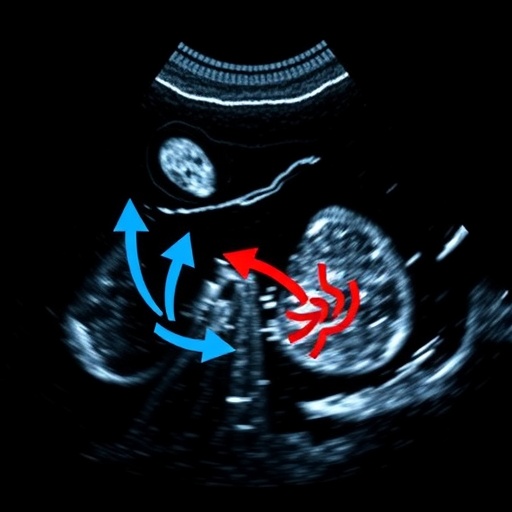

Technically, the high frame rate involves capturing ultrasound images at exceptionally rapid intervals, thereby resolving the temporal resolution barriers that have limited previous contrast-enhanced ultrasound applications. This capability facilitates detailed real-time tracking of contrast agents as they traverse tumor microcirculation, revealing intricate vascular patterns that are invisible to standard imaging techniques.

The vascular morphology evaluation hinges on sophisticated image analysis discerning the branching complexity, density, and distribution of microvessels within the tumor matrix. Arborescent patterns reflect a tangled, irregular vasculature often associated with neoangiogenesis—a hallmark of malignant progression—while fine vascular patterns denote sparse and orderly vessel architecture, indicative of less aggressive pathology.